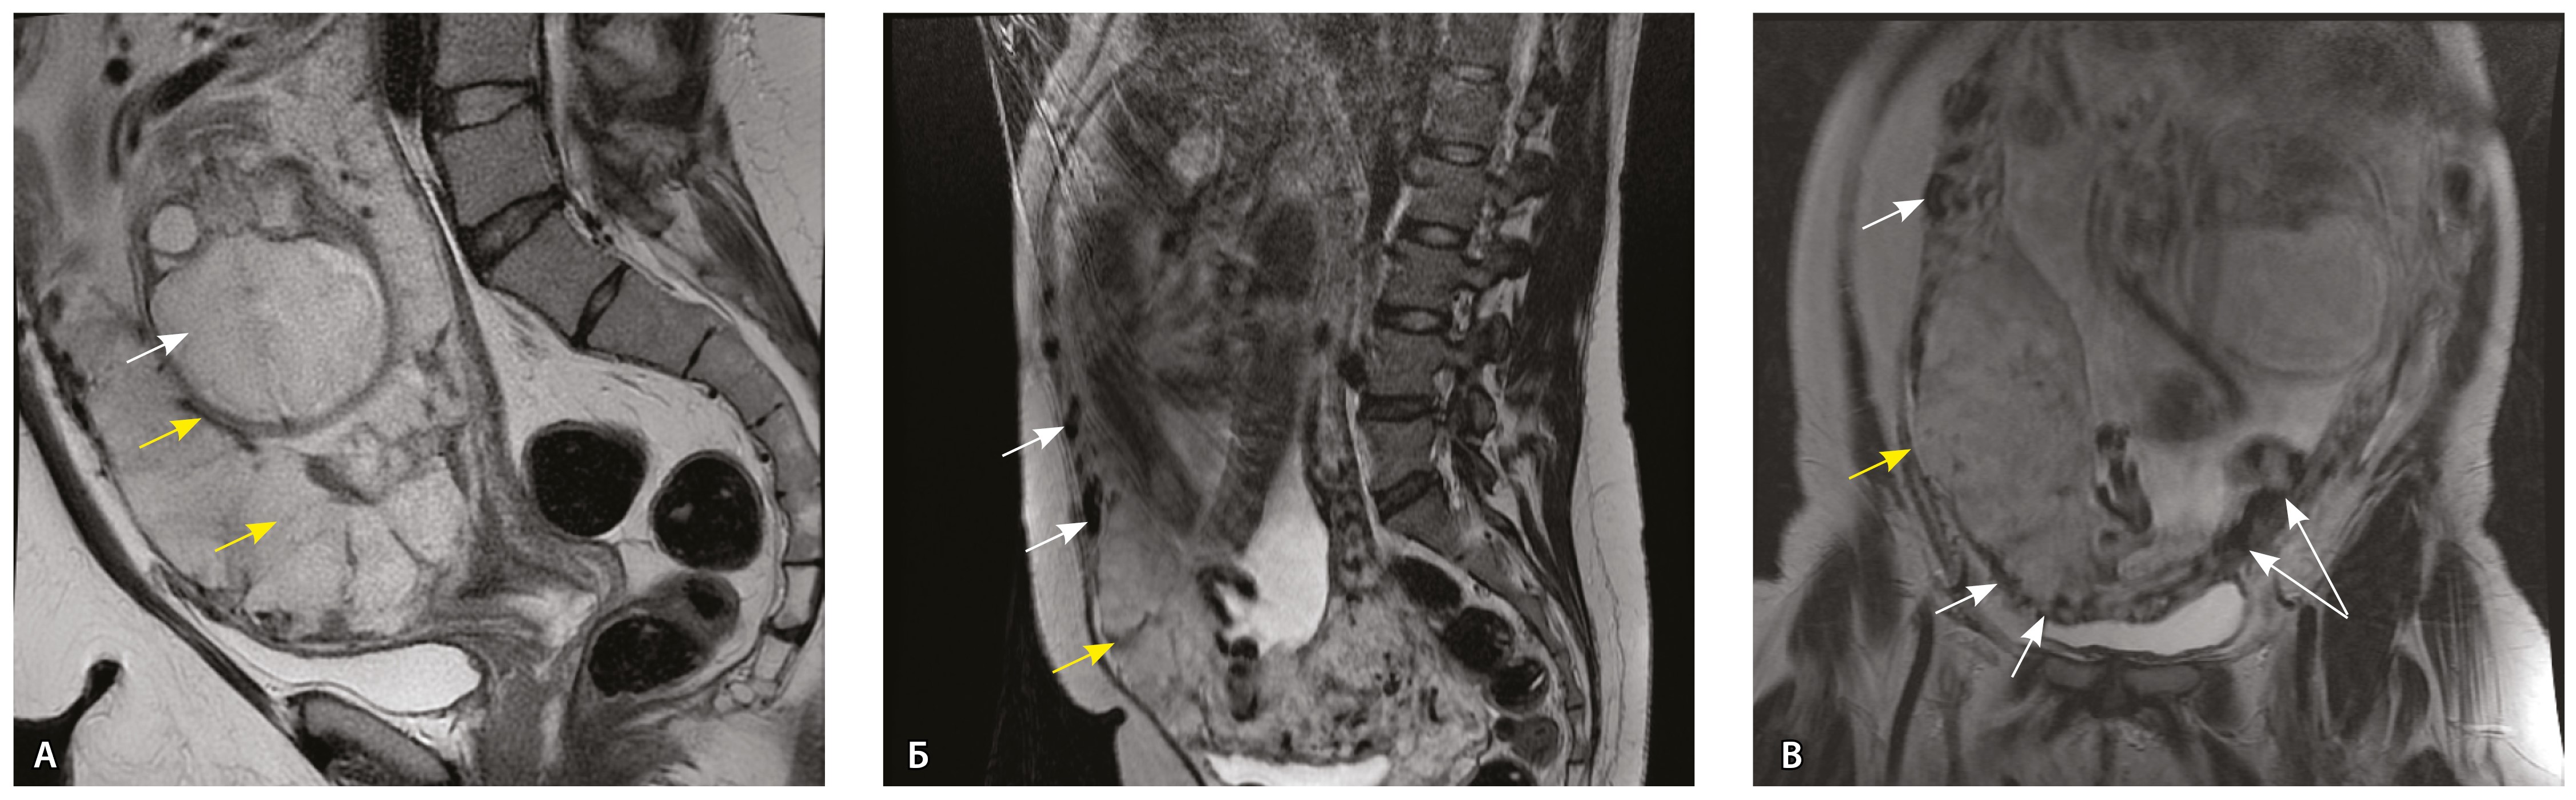

Сосуды 4-го типа. Наличие крупных извитых анастомозирующих сосудов, преимущественно по поверхности матки (в составе серозной оболочки матки) в сочетании с выраженным истончением нижнего сегмента матки (рис. 10).

Рис. 10. Беременность 33 недели, pl. percreta, PAS 3a по FIGO. На магнитно-резонансных томограммах в режиме Т2-взвешенного изображения в сагиттальной (A) и фронтальной (Б, В) плоскостях определяется внутриматочная гиперваскуляризация (желтые стрелки) и гиперваскуляризация в области выраженно истонченного нижнего маточного сегмента, с наличием многочисленных анастомозирующих сосудов по поверхности матки (белые стрелки); стенка матки в данной области представлена ретроплацентарными сосудами

Главным отличием крупных сосудов в составе серозной оболочки является то, что морфологически они находятся в пределах стенки матки. Об этом свидетельствует наличие в операционном материале тонкого поверхностного слоя мезотелия, отделяющего матку от брюшной полости (рис. 11). Его невозможно визуализировать методом МРТ из-за особенностей метода и толщины получаемых срезов.

Анализ частоты встречаемости сосудов 4-го типа при различных степенях приращения плаценты (рис. 14) показал: при плотном прикреплении плаценты (gr 2) и поверхностном приращении (gr 3) сосуды данного типа не выявлены, при pl. increta (gr 4) частота встречаемости незначительная – 16,7%, а при глубокой инвазии плаценты (pl. percreta, gr 5) сосуды этого типа преобладают (р < 0,001, хи-квадрат Пирсона).

Рис. 14. Частота встречаемости сосудов 4-го типа при различной глубине приращения плаценты (grade МАPI-RADS)

Тип 4. Истончение нижнего сегмента матки вследствие значительного выбухания плаценты, повреждения, некроза и некробиоза миометрия, достижения ворсинами серозного покрова матки, в сочетании с наличием извитых анастомозирующих артерий калибром 3–4 мм по поверхности матки, наиболее вероятно, в составе серозной оболочки (характерно для pl. increta, PAS 2 по FIGO, а также pl. percreta, PAS 3a по FIGO).

Сосуды 4-го типа встречались как при pl. increta (16,7%) (PAS 2 по FIGO), так и при pl. percreta (100%) в пределах серозного слоя матки (PАS 3a по FIGO). Обнаружено наличие крупных извитых анастомозирующих сосудов, преимущественно по поверхности матки, в сочетании с выраженным истончением рубца от КС. Главное отличие сосудов этого типа – локализация в пределах серозного слоя матки, с наличием тонкого поверхностного слоя мезотелия на микропрепаратах по их поверхности. Этот феномен можно объяснить тем, что в случае прикрепления трофобласта и затем плаценты к рубцу от КС при прогрессировании беременности плацента оказывает паракринное влияние в том числе посредством факторов ангиогенеза, в результате чего нельзя исключить рост сосудов из бассейнов маточных артерий с целью обеспечения трофической функции матки и сохранения беременности. Указанный патогенетический механизм также подтверждают описанные в литературе случаи брюшинной беременности [17]. Кроме того, нельзя исключить, что локальная ишемия стенки матки в области врастания может способствовать увеличению ангиогенеза и васкулогенеза. При выполнении МРТ невозможно достоверно визуализировать серозный слой матки из-за его малой толщины, поэтому создается впечатление о локализации сосудов за пределами стенки матки. По данным патоморфологического исследования, для этого типа характерно наличие крупных сосудов, анастомозирующих друг с другом. В стенках артерий трудно различимы 2 слоя миоцитов, по наружной поверхности сосуды окружены толстым «футляром» из грубоволокнистой соединительной ткани, которая проникает в стенку артерий и замещает мышечный слой. Эластический каркас представлен сетью тонких волокон, без концентрации на внутреннюю и внешнюю мембраны. Генез возникновения таких сосудов до конца не изучен. В ряде исследований, посвященных беременности, расположенной в проекции рубца от КС, отмечается наличие артериовенозных соустий по типу мальформации в данной области даже на ранних сроках беременности, которые, возможно, продолжают функционировать и на более поздних сроках и становятся еще более полнокровными [18–20].